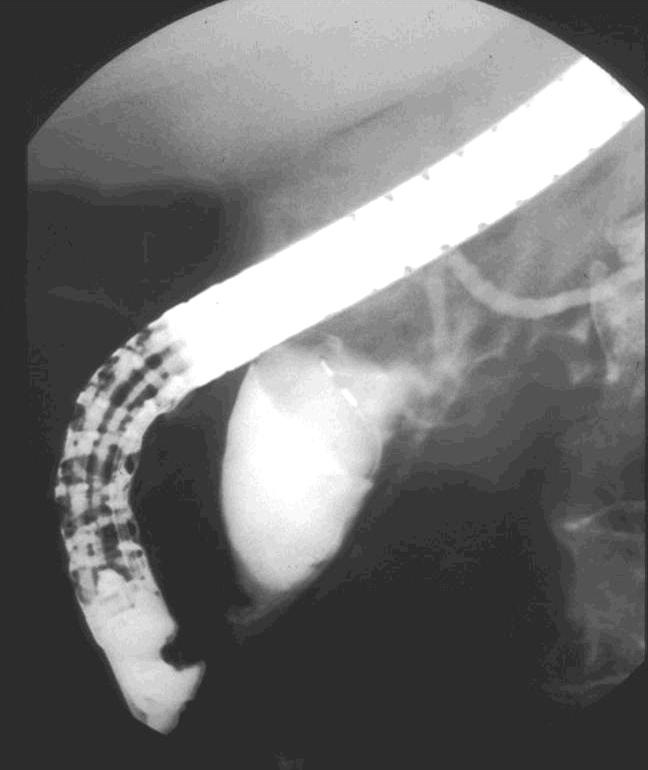

Hilar Nodal Metastases

Extra-Hepatic MetastasesPrimary